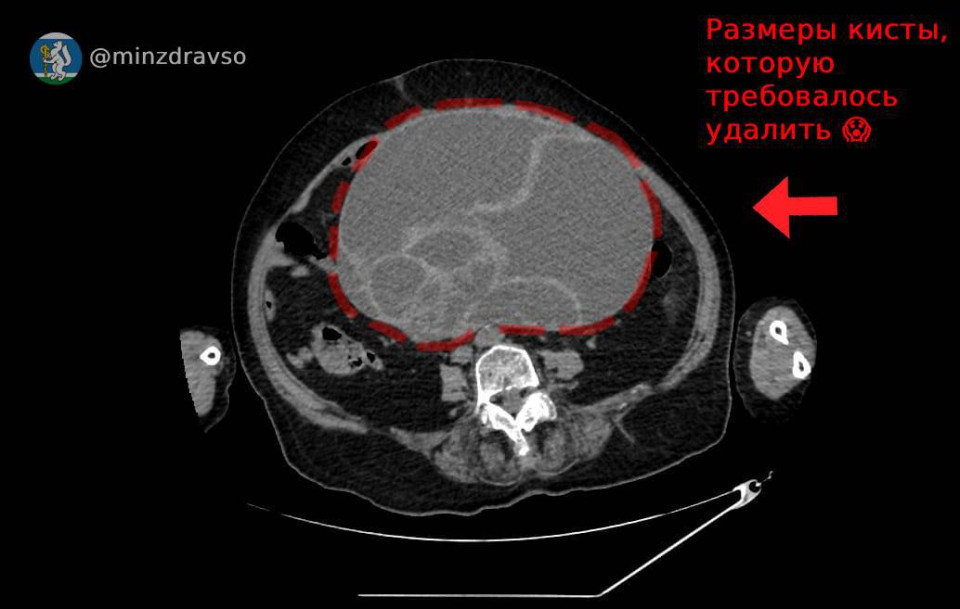

Специалисты Красноуфимской районной больницы спасли 86-летнюю пациентку с кистой весом 4,5 кг, сообщает региональный минздрав.

Доброкачественная опухоль размером 32×25×22 см сдавила все внутренние органы.

«В ходе операции медики избавили свердловчанку от объемного новообразования», — говорится в сообщении.